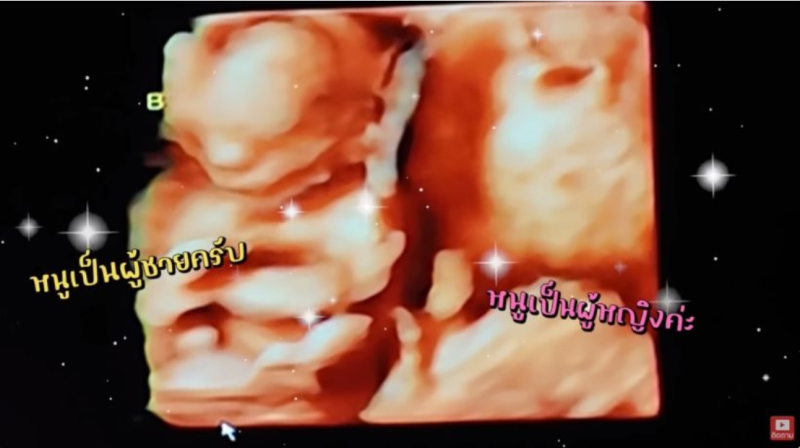

โดยในช่อง Youtube DanPattie เวลามา 3 เดือนเริ่มเห็นเพศชัดเเล้ว ซึ่งเเดนเเละเเพทตี้บอกเลยว่าตื่นเต้นเเละดีใจสุดๆ เมื่อลูกในท้อง ได้ชายคนหญิงคนมาเเบบครบจบท้องครั้งเดียว